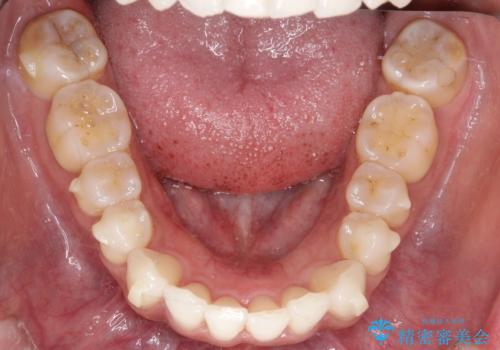

【インビザライン】前歯の凸凹をIPRで改善

- 前歯の凸凹を主訴に来院されました。

前歯を並べるために歯と歯の間にヤスリを入れてわずかに歯を削ることでスペースを確保しています。

歯と歯の間にヤスリを入れてわずかに歯を削ることでスペースを確保する処置をIPRと呼びます。

当院では拡大鏡を用いて丁寧に処置することで歯冠形態を損なわずに行うことができます。